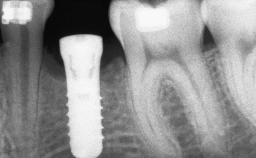

# of Implants 8

Type of Implants Reduced-Diameter|Two-Piece

Bone Augmentation Horizontal|Sinus Floor Elevation|Staged|Vertical

Augmentation Materials Autogenous chips|Autogenous block(s)